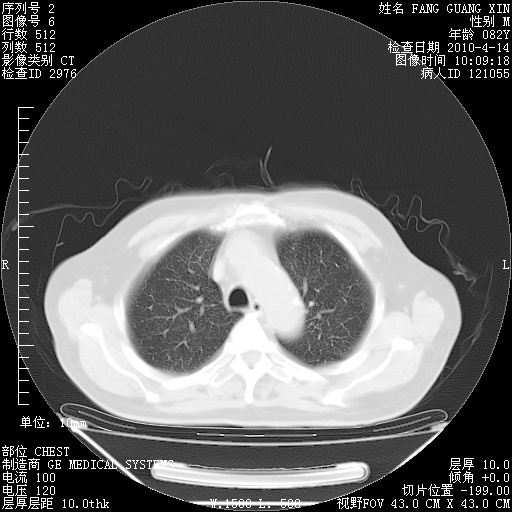

4月14日肺部CT

肺部CT平扫未见异常。